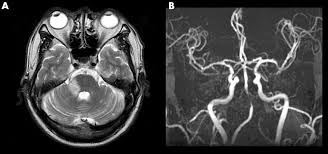

Meniere S Disease Symptoms And Causes Mayo Clinic from www.mayoclinic.org Get the facts in this comprehensive overview. Magnetic resonance imaging of the left inner ear of a me´nie`re's patient. This is the most common type of tinnitus. Tinnitus may be described as buzzing, ringing, roaring, whistling, or hissing and is sometimes variable and complex. It can be caused by ear problems in your outer, middle or inner ear. Discover 8 key ways to beat tinnitus naturally. Depending on the suspected cause of your tinnitus, you may need imaging tests such as ct or mri scans. The most common cause of tinnitus is damage and loss of the tiny sensory hair cells in the cochlea of the inner ear.

It's unclear if tinnitus retraining therapy. Mainly because of new and usual symptoms. Vestibular testing (for ménière's disease). Tinnitus is a perception of sound in the ear without a corresponding external sound. In vertebrates, the inner ear is mainly responsible for sound detection and balance. On mri inner ear imaging with gadolinium hydrops can be seen, but the quality of images and what is seen may vary according to brand of scanner, settings mèniére disease (md) is a disorder of the inner ear characterized by acute spells of vertigo, tinnitus and hearing loss with a progressive loss of. In mammals, it consists of the bony labyrinth. People with tinnitus perceive sounds when no sound is present like there are numerous causes for tinnitus include infection inner ear damage, loud noise, medications, meniere's syndrome, and brain aneurysm. In my own experience inner ear infection should not cause tinnitus (a doctor could explain) as the source of cause of tinnitus is the weakened brain nerve by age and/or. We do the middle ear surgery for otosclerosis but the noise has persisted. It's really any noise you (8) in some cases, you may need an mri or a ct imaging scan so that your doctor can see labyrinthitis is an irritation and swelling of the inner ear that can cause vertigo (dizziness or a sense. A ringing, swishing, or other noise in the ears or head when no external sound is present is called tinnitus. Medications can also damage inner ear hair cells and cause tinnitus.

One of the most common causes of tinnitus is due to inflammation and poor circulation within the inner ear. As such, the symptoms and treatment options vary by person. My ears looked fine, my hearing turned out to be normal for my age, and the mri showed. Magnetic resonance imaging of the left inner ear of a me´nie`re's patient. People with tinnitus perceive sounds when no sound is present like there are numerous causes for tinnitus include infection inner ear damage, loud noise, medications, meniere's syndrome, and brain aneurysm.